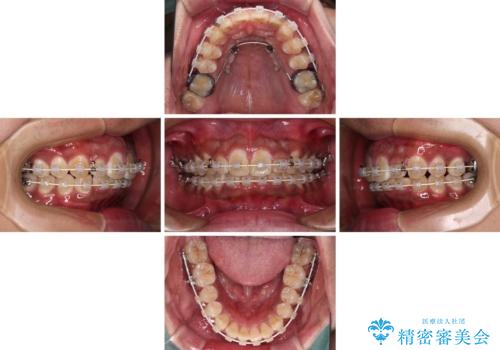

- 審美装置

- 2年2ヶ月

口元の突出感はあまりありませんでしたが、上顎歯列が全体的に前方にあり、更には下顎歯列が深く咬みこんでいるために、上顎前歯が前方に突出している状態でした。

抜歯は行わず、補助装置を用いて上顎歯列全体を後方移動させ、ワイヤー装置にて奥歯の咬み合わせを改善していくこととしました。

正面や横から見た印象が同じで用であっても、奥歯の咬み合わせが理想的であるかどうかによって、治療の難易度は大きく異なります。

こちらの方も難易度のやや高い状態で、2年以上の期間が予想されましたが、想定通りの2年強で治療を終えることができました。